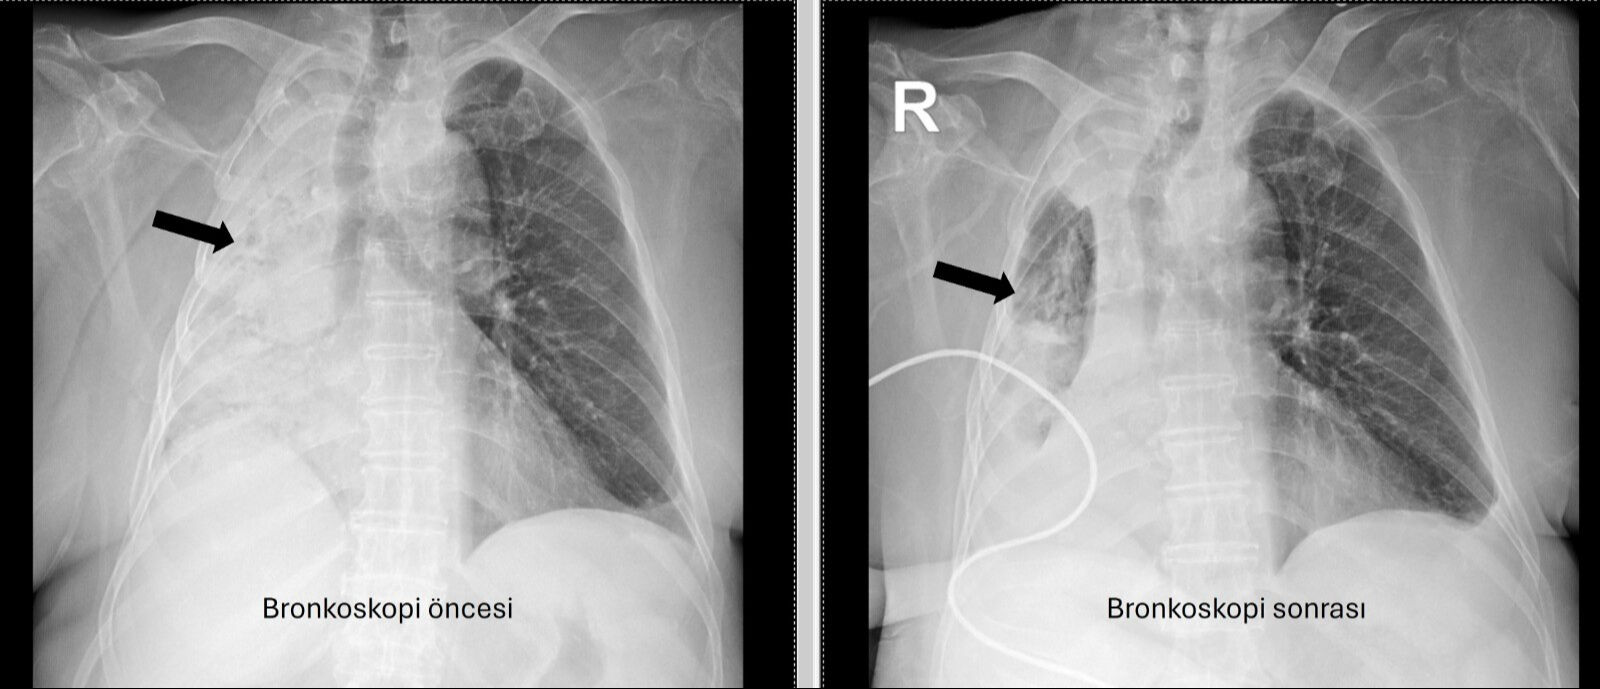

Pamukkale Üniversitesi (PAÜ) Hastaneleri Göğüs Hastalıkları Anabilim Dalı Öğr. Üyesi Prof. Dr. Göksel Altınışık Ergur tarafından yapılan tetkiklerde, felçli kadının sağ akciğere giden hava yolunun bütünüyle kapalı olduğu görüldü. Hastaya acil bronkoskopi planlandı ve işlem gerçekleştirildi.

Yapılan müdahalede, solunum yolunu tıkayan cismin bir 'mısır tanesi' olduğu belirlendi ve cisim, aspiratör yardımıyla başarıyla çıkarıldı. Uzmanlar, cismin muhtemelen 5 ay önce yediği pizzadan solunum yoluna kaçtığını belirtti.